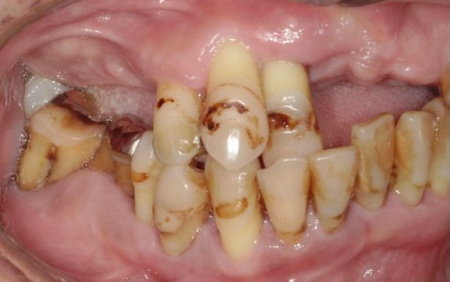

「転倒して上前歯のブリッジがとれた。他院で上あごの総入れ歯をすすめられたが、ほかに方法がないか知りたい」とセカンドオピニオンとしてご来院いただきました。

拝見したところ、患者様は上前歯が数本欠損しており、残っている歯を利用して橋渡しのように歯を補うブリッジ治療が行われていました。しかし、転倒による衝撃でブリッジが外れていました。

このまま放置すると見た目への影響だけでなく、食事をしっかりとることが難しくなるなどの問題が生じる可能性があります。

また、患者様は重度の歯周病によって歯を支える骨が減少し全体的に歯が揺れていました。

残っている上の歯7本(左右上側切歯、左右上犬歯、左右上第1小臼歯、左上第1大臼歯)と右下奥歯2本(第2大臼歯、第3大臼歯)は残すことが難しく抜歯が必要な状態です。